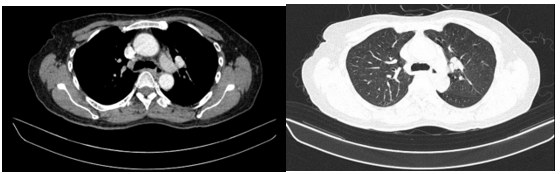

Hình 1. Hình ảnh sỏi đường mật tạo ổ áp xe gan - đường mật gan trái (vòng tròn màu đỏ). Giãn nhẹ đường mật trong gan hai bên. Dày thành nhẹ ngã ba đường mật trên phim chụp cắt lớp vi tính.

Đánh giá tổn thương trên phim chụp cộng hưởng từ: Nhu mô hạ phân thuỳ IV có ổ tổn thương dạng dịch, kích thước 38x52mm, trong có vài sỏi, sỏi lớn nhất kích thước ~27x37mm, có thông với nhánh đường mật gan phải lân cận, ngấm thuốc viền sau tiêm, chèn ép ngã ba đường mật, gây giãn đường mật trong gan hai bên

Hình 2. Hình ảnh giãn khu trú đường mật gan trái, tạo cấu trúc dạng nang và sỏi đường mật bên trong( vòng tròn đỏ), chèn ép kèm giãn đường mật trong gan hai bên trên phim chụp MRI

Hình ảnh chụp cắt lớp vi tính ngực: Dải xẹp phổi rải rác thuỳ dưới hai phổi. Nhu mô còn lại đồng nhất, không thấy tổn thương khu trú hoặc lan tỏa. Không thấy tổn thương hình mờ dạng lưới. Không thấy giãn phế quản – phế nang.

Hình 6. Phim chụp cắt lớp vi tính chưa phát hiện tổn thương thứ phát.